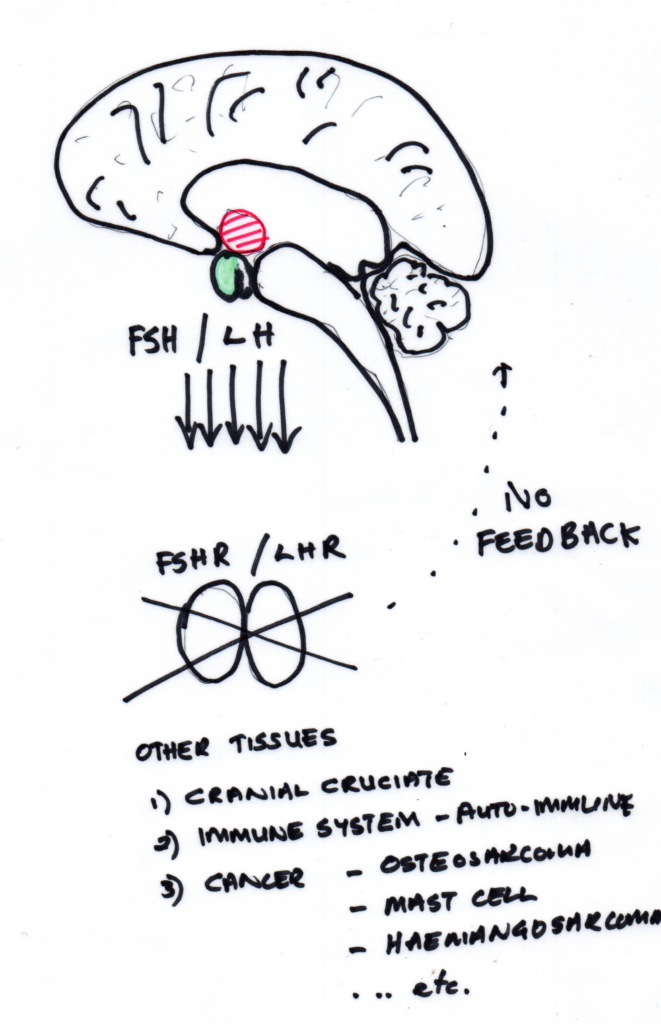

Biological Focus: HPG Axis and LHR

Existing literature suggests possible links between:

- Post-desexing endocrine shifts

- Gonadotrophin signalling

- Connective tissue integrity

For this reason, hypothalamic–pituitary–gonadal (HPG) axis signalling—specifically luteinising hormone receptor (LHR) expression—was selected as a biologically plausible focus for correlation.axis involvement, and specifically luteinising hormone receptor (LHR) expression, was selected as a biologically plausible focus for correlation. Images below show the hormones in an entire patient and a desexed patient.

During the correlation phase, screening outputs indicating HPG-axis reactivity were compared with:

- Surgically confirmed CCr rupture

- Immunofluorescent detection of LHR expression in cruciate tissue

This was a correlation study, not a diagnostic validation trial.

The objective was to assess alignment between repeatable functional response patterns and tissue-level biological markers.s whether repeatable functional response patterns aligned with biological markers present in diseased tissue.